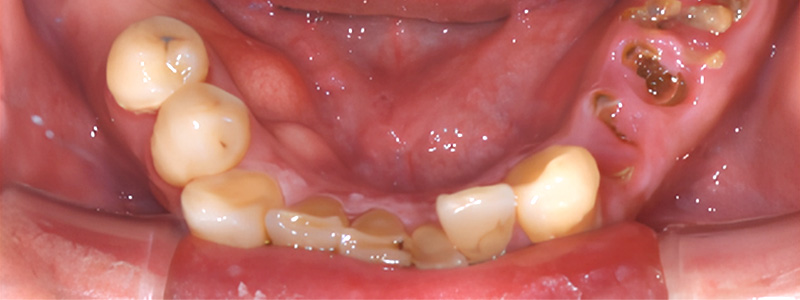

- 治療名

- インプラント治療ジルコニアクラウン

- 治療内容

- 左右臼歯にインプラント治療を行い、残存歯にジルコニアクラウンを製作。

- 患者様

- 40代男性

- 治療期間

- 約9ヶ月

- 費用

- ¥3,146,000

- 治療に対するリスク

- 外科治療に伴う術後疼痛合併症のリスク

- 執刀医

- Dr.村尾